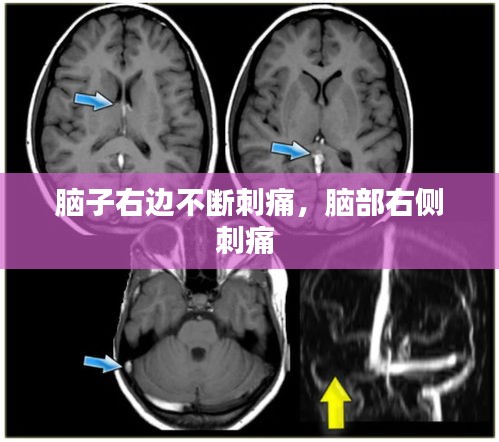

为了确诊,我决定去医院进行详细的检查。医生为我进行了脑部CT扫描、颈椎X光片以及神经系统检查。结果显示,我的脑部结构和颈椎均未发现异常。医生告诉我,这种刺痛感可能是由于神经紧张或肌肉紧张引起的,建议我注意休息,适当放松。